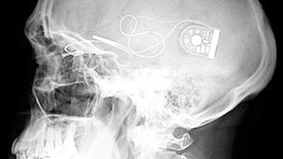

Kỹ thuật đặc biệt giúp người đàn ông tìm lại nụ cười sau hơn một năm bị co giật nửa mặt